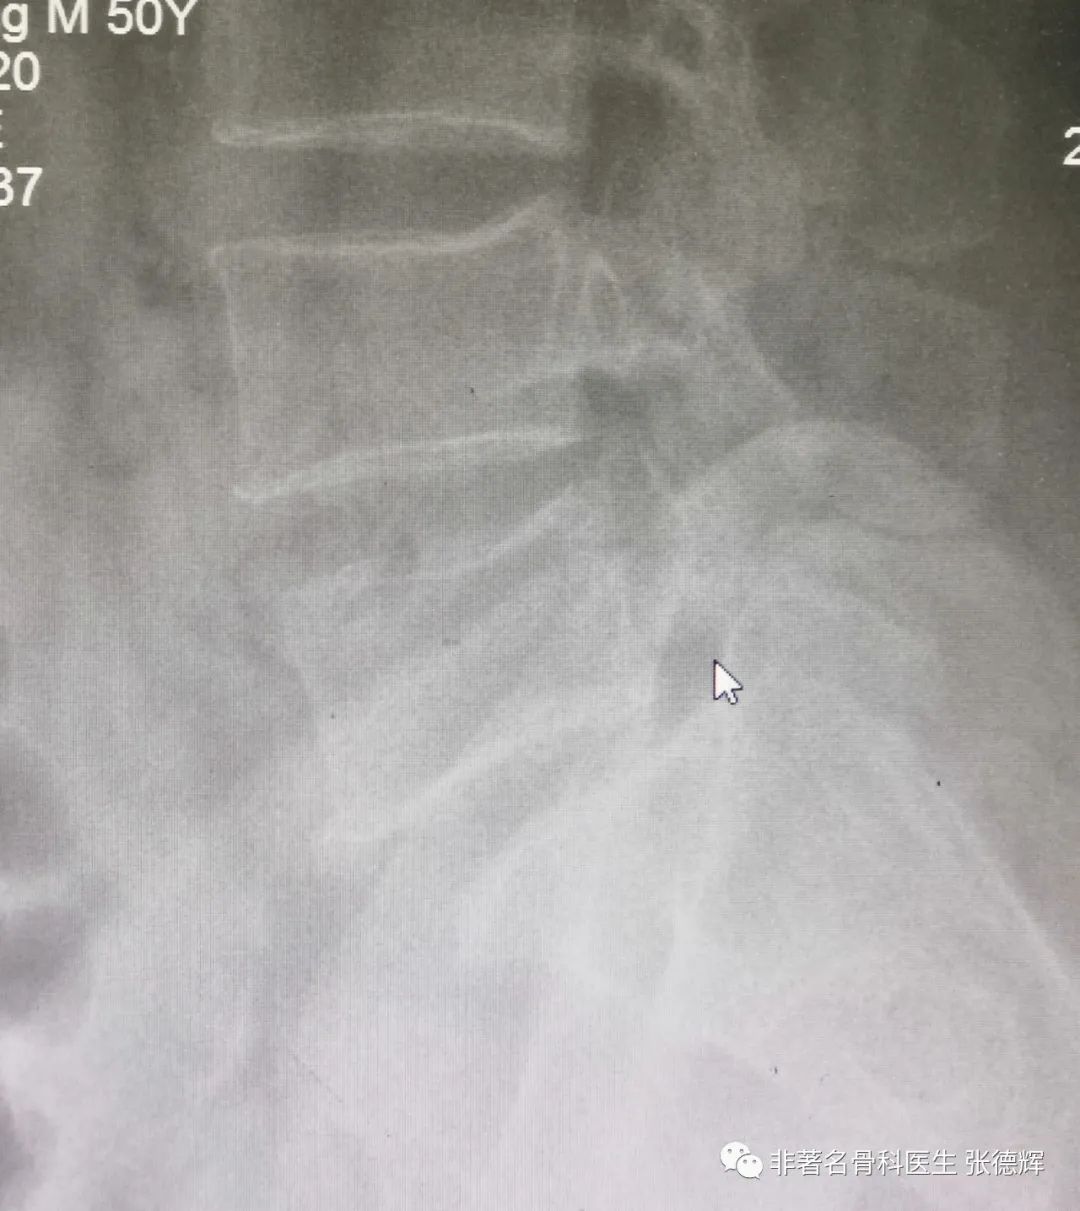

近期接诊一位腰椎峡部裂的患者,体重接近100公斤,腰腿痛近1年,严重时行走障碍,以下是影像检查资料。可以看到是明显的 腰5双侧峡部裂并轻度滑脱 。

腰椎侧位片可见腰5轻度向前滑移